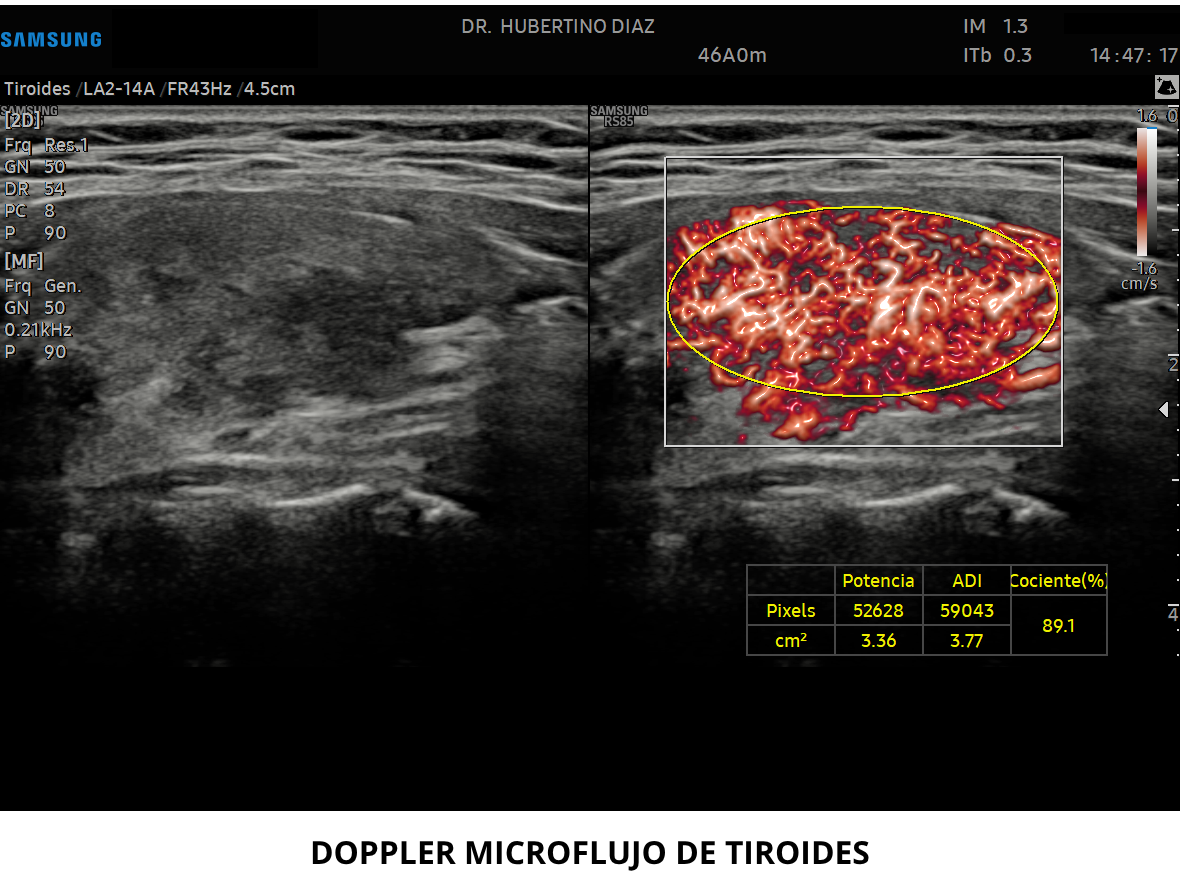

ECOGRAFÍA DOPPLER DE TIROIDES

El estudio Doppler es un parámetro de evaluación de suma imp...